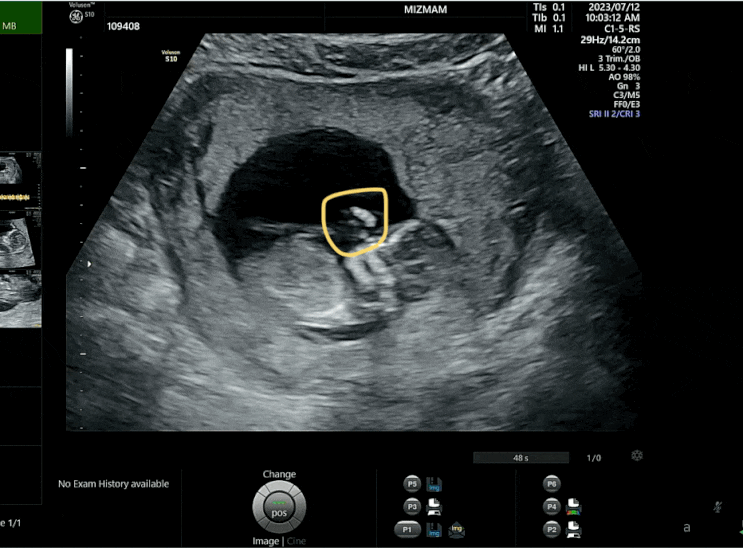

2023. 07. 12 (수) 드디어! 분만병원으로 전원을 결정하고 첫 진료를 봤던 날. 7월 12일 기준으로 쑥쑥이는...